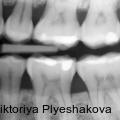

Nichtchirurgische Therapie tiefer PA-Defekte mit NaOCl-Gel und vernetzter Hyaluronsäure